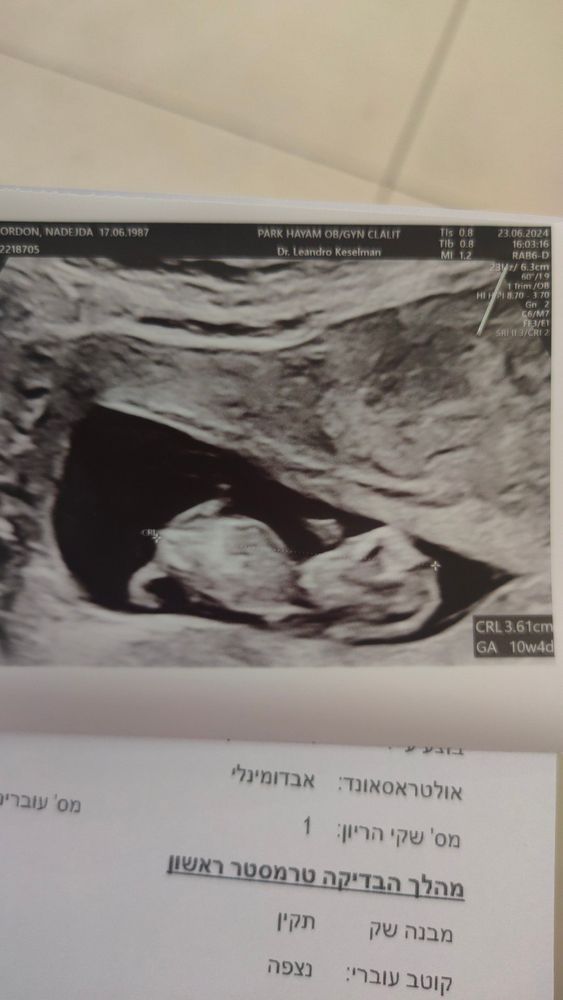

ИзображениеВот наша самая свежая фотка 10+4, странная конечно фотка ну да ладно, скоро на 1 скрининг будет точно что-то удачнее.